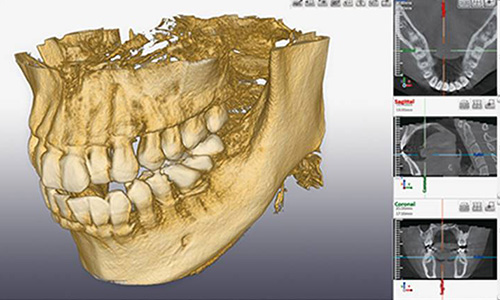

当院では、院内にCT設備も完備しておりますので、そもそも親知らずを抜いた方がいいのかどうか、抜く場合は痛みや腫れのリスクはどのくらいあるのかなど、精密に分析することが出来ます。

隠れたリスクも洗い出す、CTによる精密分析

レントゲン写真では、親知らずの歯がどのように顎の骨に埋まっているのか、神経が親知らずと接触しているかどうかの確認が正確に行えないため、CT撮影をして親知らずの埋まり方や歯根の形、神経や血管との距離など正確に診断する必要があります。

また歯茎に埋まっている親知らずや横向きに生えている親知らずも、根の先と下顎管が近接しているケースが多いため、抜歯の際にはCT撮影による事前の綿密な診査診断がとても重要です。